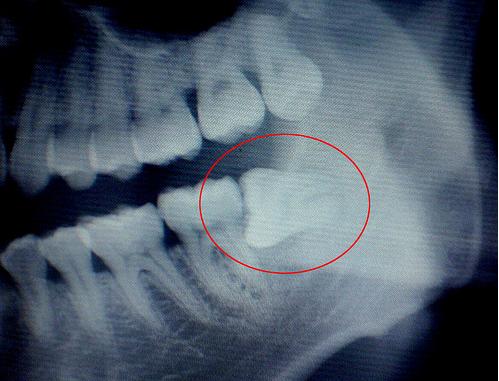

原因就是人类的进化,食物精细化,脸逐渐变窄,颌骨缩小,整个口腔呈慢慢变小的趋势。但是你要知道牙齿的数目和大小没有变化,而且智齿长出来比较晚,等它长出来的时候,其他28颗牙齿已经先入为主了,空间基本占满了,所以智齿没有足够的空间,只能以各种姿势出现在口腔中。横着、斜着、躺着、竖着、歪着、挤着,怎么舒服怎么来。

这图片是阻生智齿,也就包括横着长的智齿拔除,会比较复杂些,平常简单的拔牙就是用工具将牙齿拔掉,不用缝线,上个药就搞定啦。